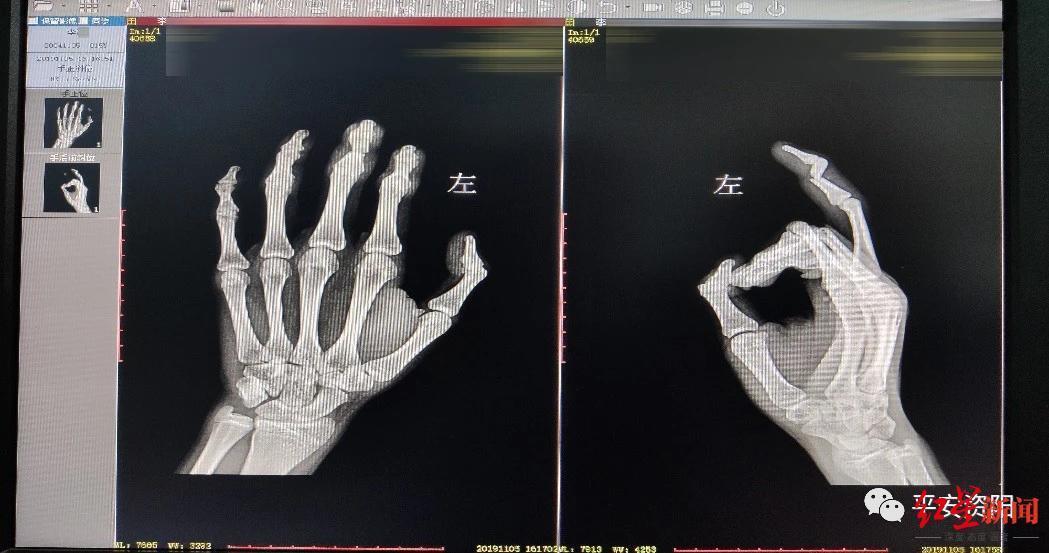

↑被敲成骨折的手指。